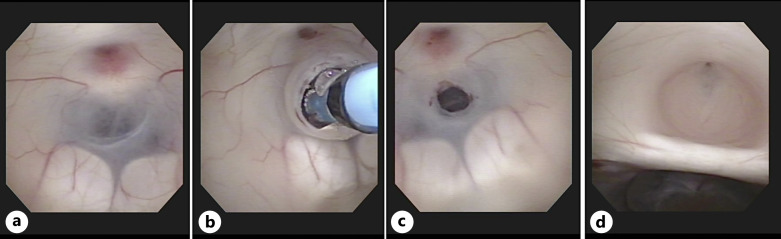

Case presentation: A 16-year-old girl with no relevant medical history presented with a 1-week history of binocular diplopia without any loss of visual acuity in either eye. At the time of her visit, she had no symptoms of headache or vomiting. Examination of eye movements revealed bilateral abduction deficits and fundoscopic examination showed bilateral optic disc swelling. Non-contrast computed tomography of the head indicated hydrocephalus. Contrast-enhanced magnetic resonance imaging of the head revealed significant dilatation of the lateral and third ventricles but not in the fourth ventricle. Sagittal T2-weighted imaging with constructive interference in the steady state showed membranous occlusion of the cerebral aqueduct. The patient underwent an endoscopic third ventriculostomy. Binocular diplopia improved during the early postoperative period.